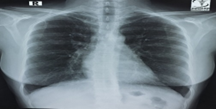

On physical examination, she was ill looking and did not have any cyanosis. Her pulse rate was 92 beats/min, blood pressure was 110/70 mmHg, and she had a normal respiratory rate with SpO2 of 97% at room air. On auscultation, the P2 component of the second heart sound was loud, and there was a systolic murmur in the left lower sternal area, no added sound in both lung fields. There was no hepatomegaly, distended veins, or neurological deficit. All biochemical reports showed normal. An electrocardiogram showed sinus tachycardia. Chest x-ray P/A view showed increased pulmonary vascularity.

Figure 1: CXR P/A view showed increased pulmonary vascularity.